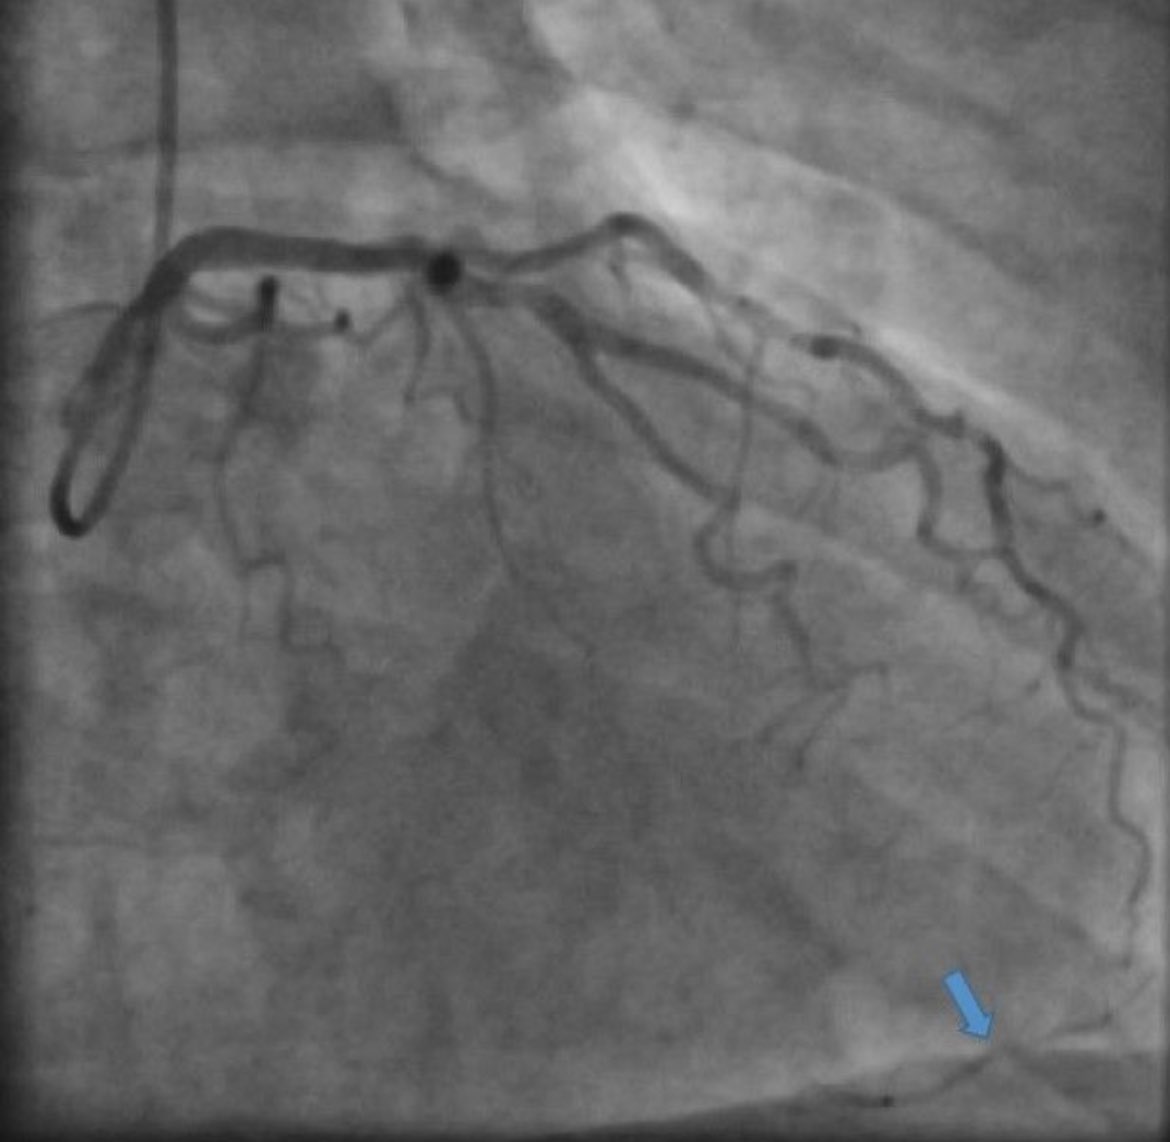

🚀 All-arterial, off-pump, no-touch aorta CABG 👨⚕️ 51y obese pt, RCA CTO, 3 failed CTO-PCI, CCS III angina, wanted durable solution w/o sternotomy. ✅ Approach: • LIMA+RIMA (I composite graft)→ PDA • MICS access ✨ Results: • Uneventful course • Home on POD 4

3

6

41